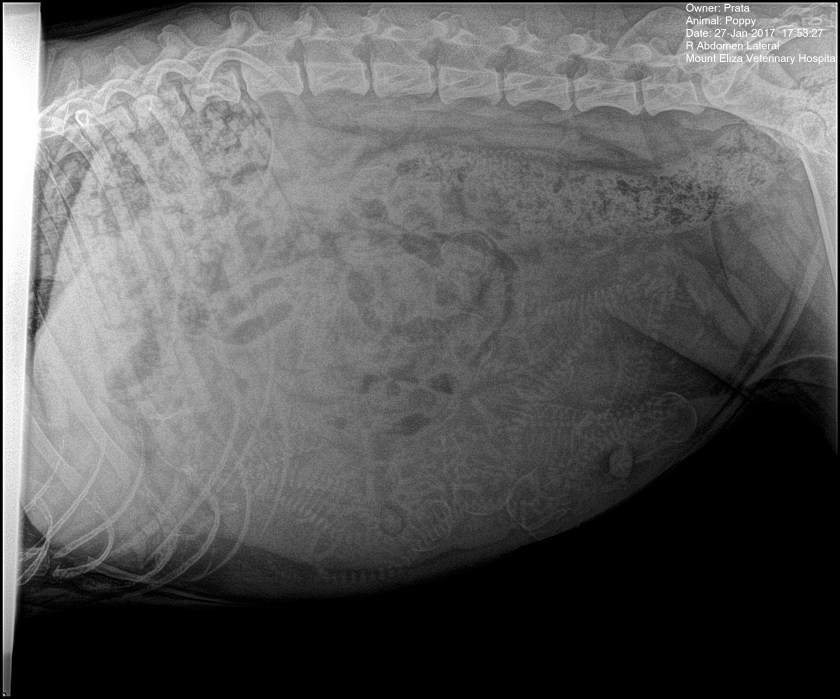

Poppy’s first litter

Poppy’s first pregnancy